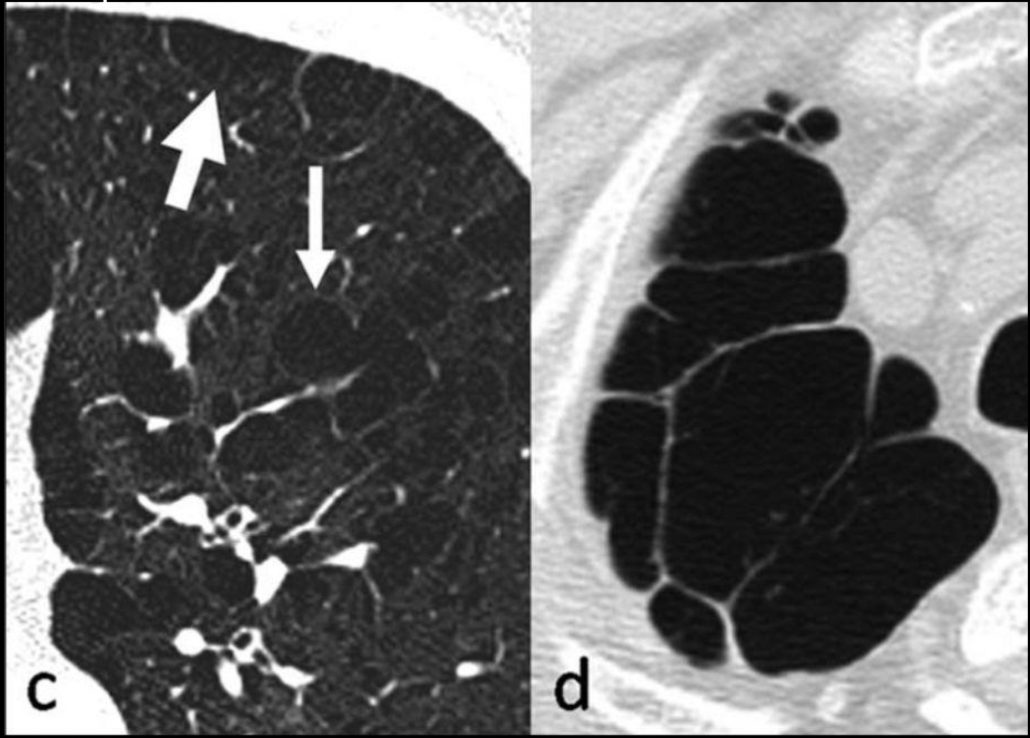

13

Q

¿Qué patrón es, qué signo es y de qué enfermedad es?

A

• Bronquiectasia

• Rieles de tren

• Bronquitis crónica

14

¿Qué signo es y que enfermedad lo tiene?

Manguito peribronquial

Bronquitis crónica